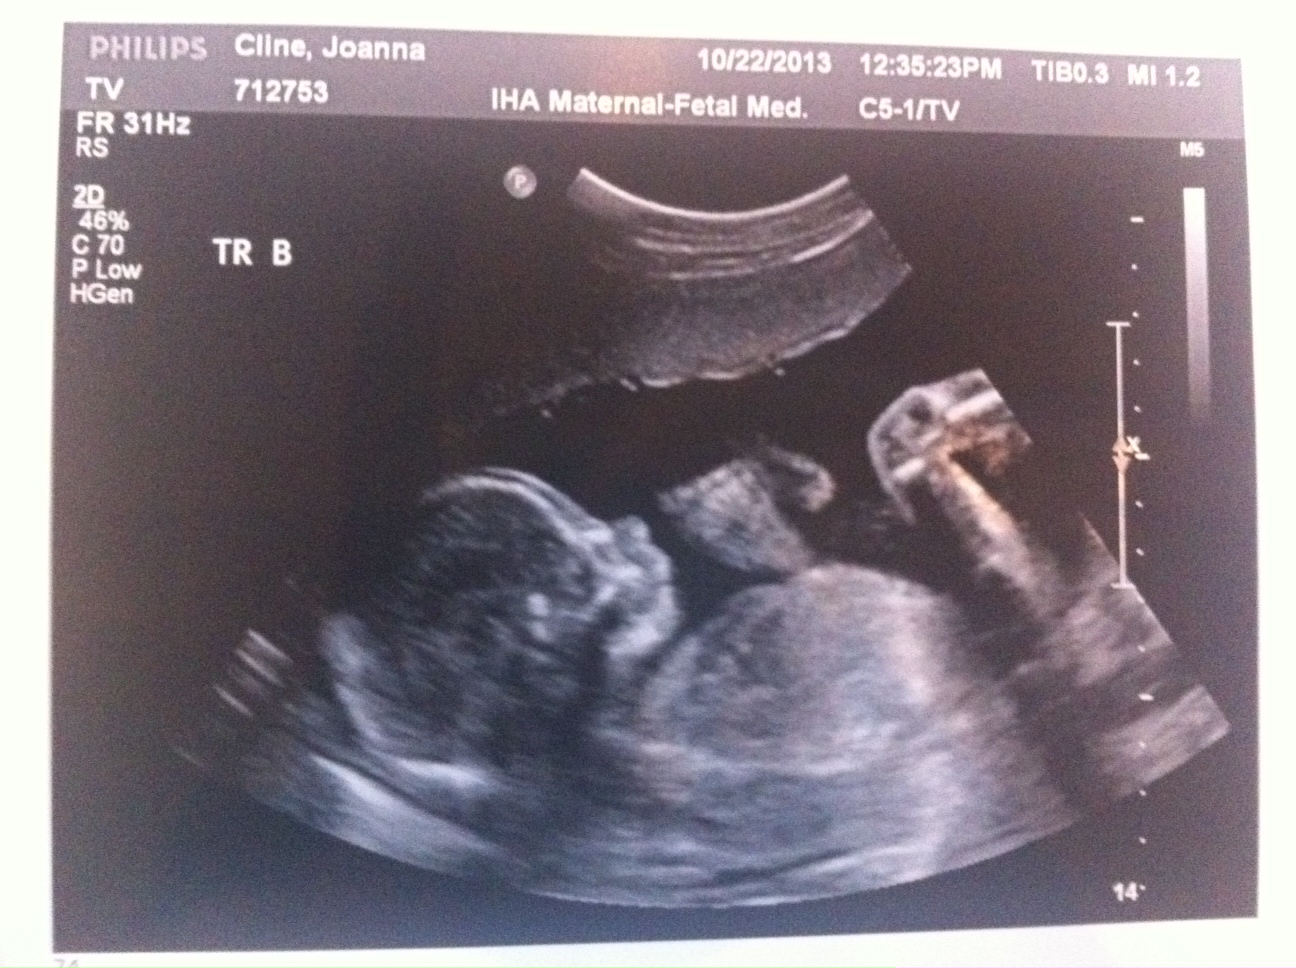

Everything still looks great. The triplets are growing but we won’t have another growth scan until my 22wk appointment. Heart beats look good and it’s clear they’re getting bigger (Today’s pictures attached.)

I’m feeling movement but mostly from triplet B. My dr said to just give it a few weeks and it will feel like a conga line in my belly.